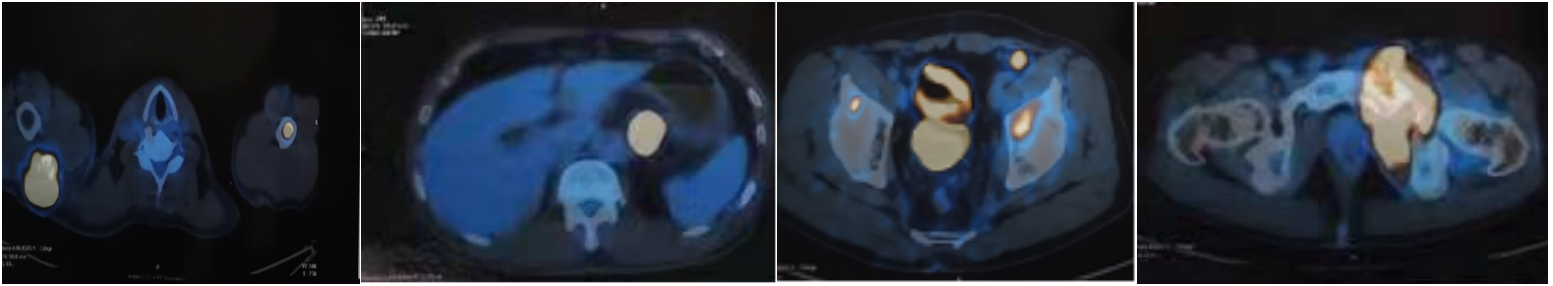

治疗约60天后,MRI对比图如下所示:

上. 三线治疗后,疾病进展后的MRI图

下. 四线治疗后,达到CR的MRI图